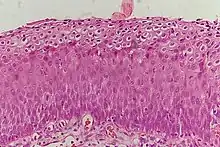

_normal_squamous_epithelium.jpg.webp)

Historically, abnormal changes of cervical epithelial cells were described as mild, moderate, or severe epithelial dysplasia. In 1988 the National Cancer Institute developed "The Bethesda System for Reporting Cervical/Vaginal Cytologic Diagnoses".[12] This system provides a uniform way to describe abnormal epithelial cells and determine specimen quality, thus providing clear guidance for clinical management. These abnormalities were classified as squamous or glandular and then further classified by the stage of dysplasia: atypical cells, mild, moderate, severe, and carcinoma.[13]

CIN is classified in grades:[14]

Histology Grade | Corresponding Cytology | Description | Image |

---|---|---|---|

CIN 1 (Grade I) | Low-grade squamous intraepithelial lesion (LSIL) |

|

![]() |

CIN 2/3 | High-grade squamous intraepithelial lesion (HSIL) |

CIN 2 (Grade II) |

![]() | |

CIN 3 (Grade III) |